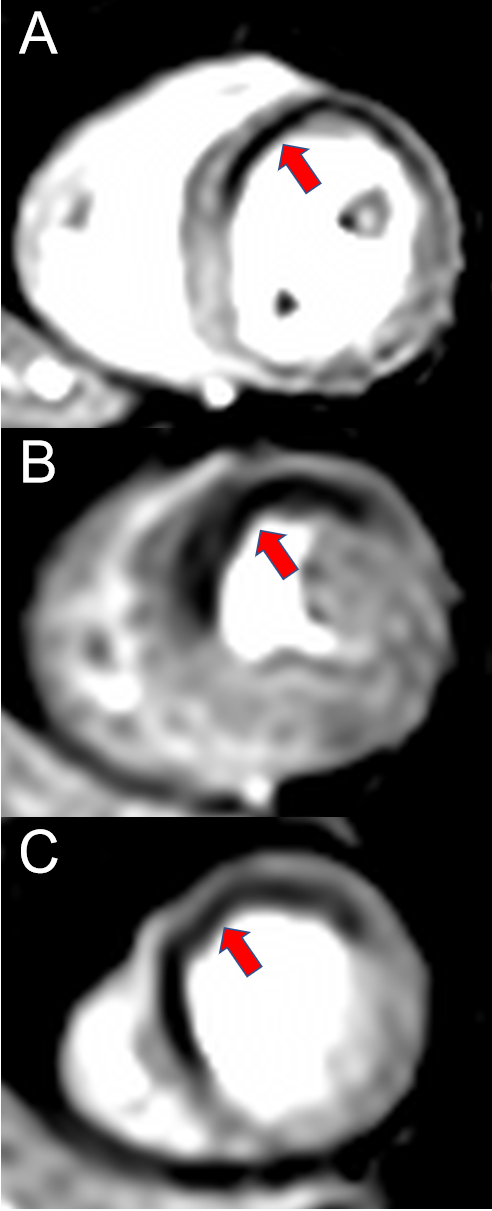

Stress CMR cannot safely exclude the presence of CAD. Its strength lies in the accurate assessment of the hemodynamic relevance of coronary stenosis, i.e., the testing for ischemia. Ischemia, however, is not a bivalent marker, but rather a continuum [27]. CAD with hemodynamically significant coronary artery stenosis leads to a decreased blood perfusion of the heart, which is dependent on the severity. During physiological or medication-induced stress, cell metabolism, diastolic function and systolic function are impaired, leading to ECG changes and ultimately symptoms such as angina or dyspnea [27]. As opposed to stress echocardiography, which usually screens for systolic wall motion deficits occurring relatively late in the ischemic cascade, perfusion stress CMR visualizes the decreased blood perfusion occurring early in the ischemic cascade [27]. In stress perfusion CMR, a vasodilator is applied, resulting in reduced myocardial perfusion in post-stenotic segments through a “steal phenomenon“(meaning that blood is predominantly directed through non-obstructed coronary arteries) and loss of autoregulation mechanisms, which is visualized by the application of a contrast agent [5,28]. Figure 1 shows an example of a perfusion deficit in perfusion stress CMR. Perfusion stress CMR has been shown to be non-inferior to invasive fractional flow reserve (FFR) with respect to major adverse cardiac events, to predict patient outcomes and to significantly reduce the need for both diagnostic and therapeutic invasive coronary angiography, thus guiding therapeutic decision making [29–32]. Apart from perfusion testing, CMR also offers an evaluation of systolic function and scar. Ejection fraction as measured by CMR is the current reference standard for systolic function due to its very low inter- and intra-rater variability (<3%) [33]. Late Gadolinium Enhancement (LGE) on the other hand is the reference standard for visualization of myocardial scar or tissue fibrosis. It may be used for targeted ablation in patients with atrial or ventricular arrhythmias or prediction of viability before revascularization [34–36]. Both have a significant correlation to patient outcome in a variety of entities and serve as early risk factors for adverse events [33,37–40]. The variety of sequences for tissue characterization as offered by CMR is of unparalleled importance in entities such as myocardial infarction with nonobstructive coronary arteries (MINOCA), myocarditis, storage diseases or cardiomyopathies [41–43].

Figure 1. Imaging example of a stress CMR. A 58-year-old female patient with atypical angina symptoms and low pretest probability was referred for a stress CMR. The stress perfusion imaging revealed an extensive perfusion deficit (red arrows) of the anterior and anteroseptal wall on the basal (A), mid-ventricular (B) and apical (C) slice. An invasive coronary angiography showed a subtotal stenosis of the proximal left anterior descending artery (LAD) and the diagonal branch.